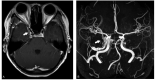

Figures